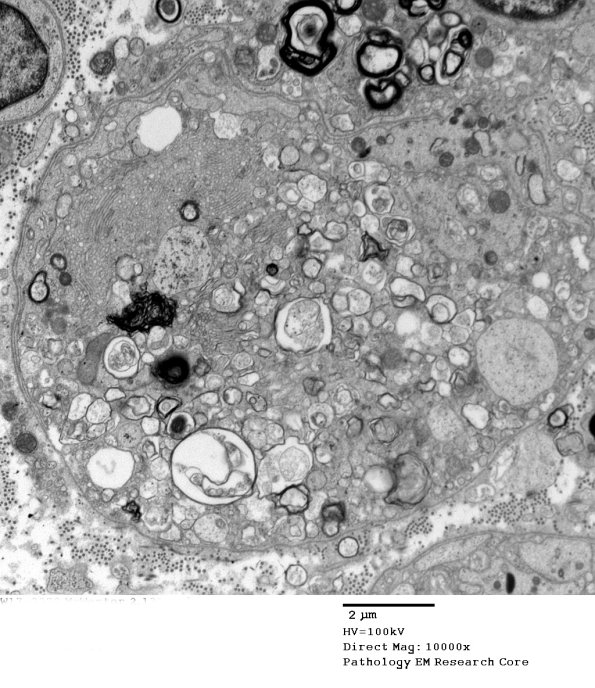

2C13,14 In this case the typical appearance of a degenerating axon shows patches of vesicular myelin.